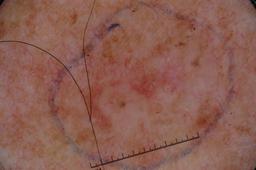

{

"age_approx": 80,

"anatom_site_general": "upper extremity",

"concomitant_biopsy": true,

"dermoscopic_type": "contact non-polarized",

"diagnosis_1": "Malignant",

"diagnosis_2": "Malignant epidermal proliferations",

"diagnosis_3": "Squamous cell carcinoma, NOS",

"diagnosis_confirm_type": "histopathology",

"image_type": "dermoscopic",

"lesion_id": "IL_7603743",

"melanocytic": false,

"sex": "male"

}